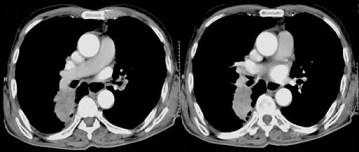

72岁,男,呼吸急促、气喘4个月,请结合胸片,选出最可能的诊断 ( )A.肺癌B.错构瘤C.肺结核D.韦格肉芽肿E.支气管腺瘤

问题 72岁,男,呼吸急促、气喘4个月,请结合胸片,选出最可能的诊断 ( )

选项 A.肺癌 B.错构瘤 C.肺结核 D.韦格肉芽肿 E.支气管腺瘤

答案 A